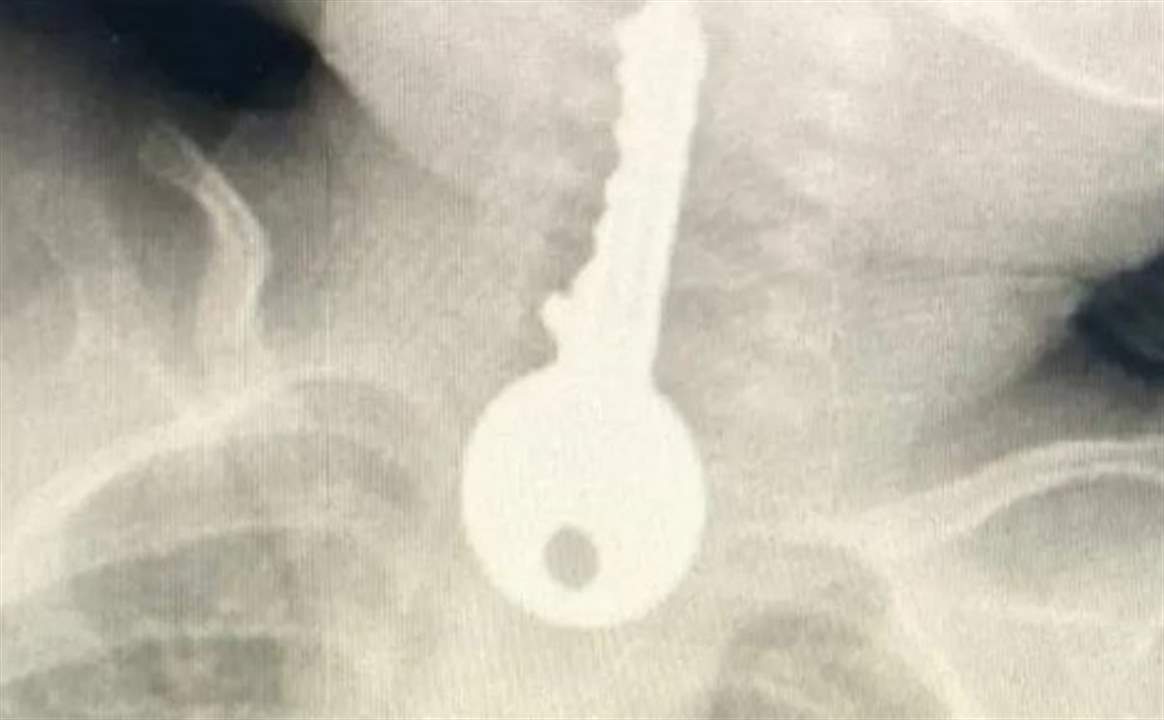

وكشفت الفحوصات وجود جسم غريب على شكل مفتاح في المريء، وعلى الفور اتخذت الإجراءات اللازمة.

الى ذلك  أوضح الفريق المعالج للحالة أنه تم على الفور عمل منظار عاجل واستخراج مفتاح حديدي من المريء كاد أن يودي بحياته.